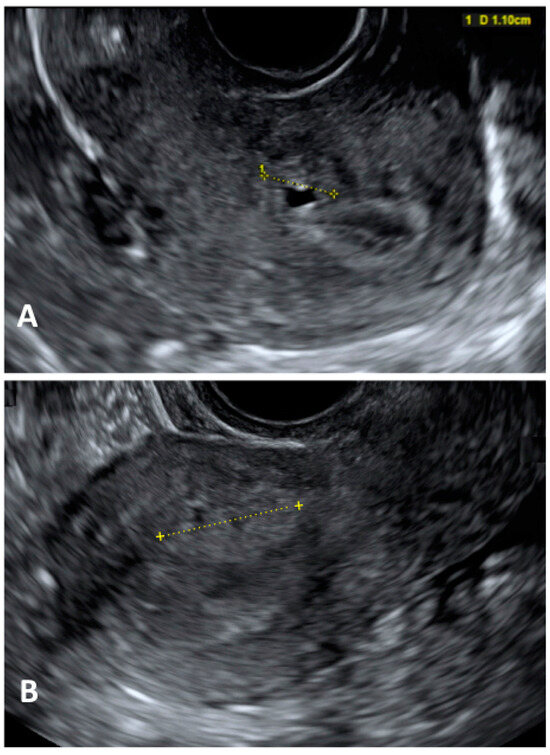

- Martire, F.G.; Lazzeri, L.; Conway, F.; Siciliano, T.; Pietropolli, A.; Piccione, E.; Solima, E.; Centini, G.; Zupi, E.; Exacoustos, C. Adolescence and endometriosis: Symptoms, ultrasound signs and early diagnosis. Fertil. Steril. 2020, 114, 1049–1057. [Google Scholar] [CrossRef]

- Martire, F.G.; Russo, C.; Selntigia, A.; Nocita, E.; Soreca, G.; Lazzeri, L.; Zupi, E.; Exacoustos, C. Early noninvasive diagnosis of endometriosis: Dysmenorrhea and specific ultrasound findings are important indicators in young women. Fertil. Steril. 2023, 119, 455–464. [Google Scholar] [CrossRef]